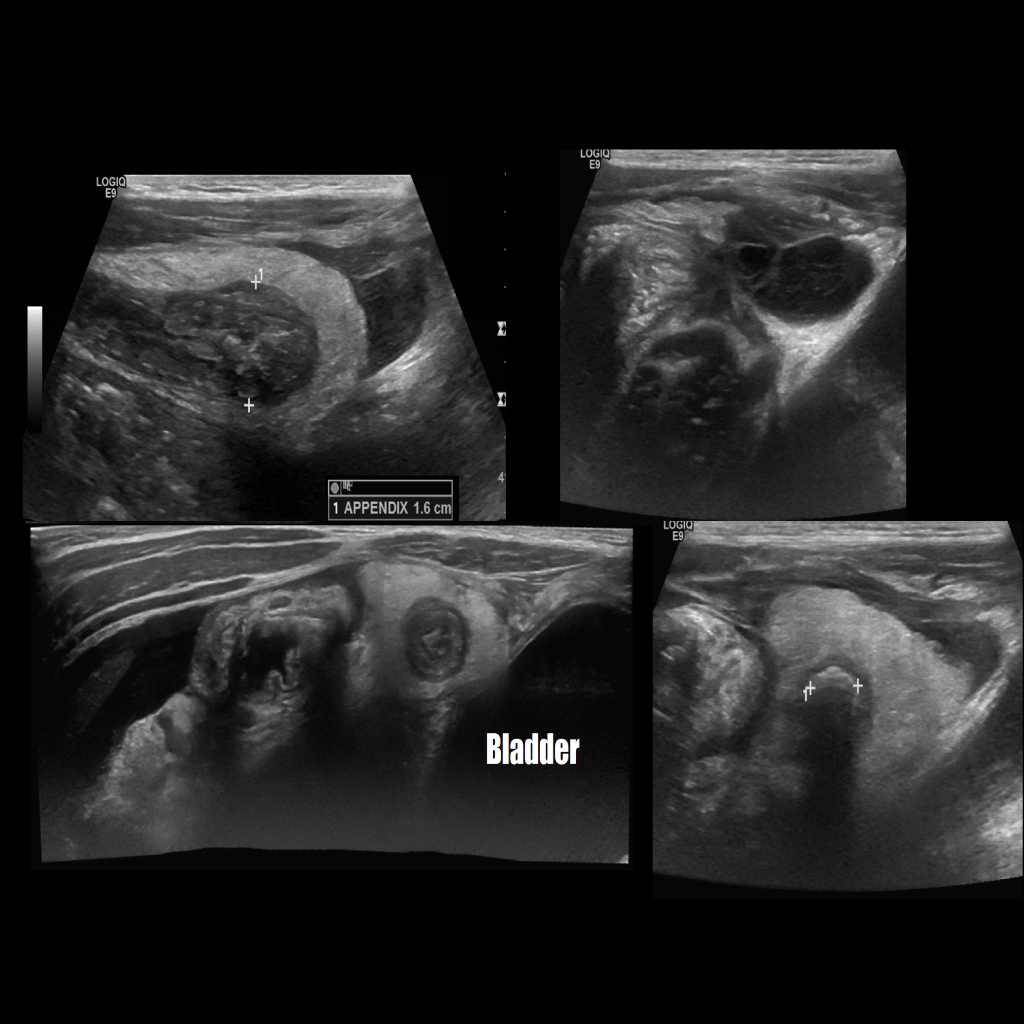

Appendicitis 8

Ruptured appendicitis with appendicolith, retrovesical and Morrison’s pouch free fluid